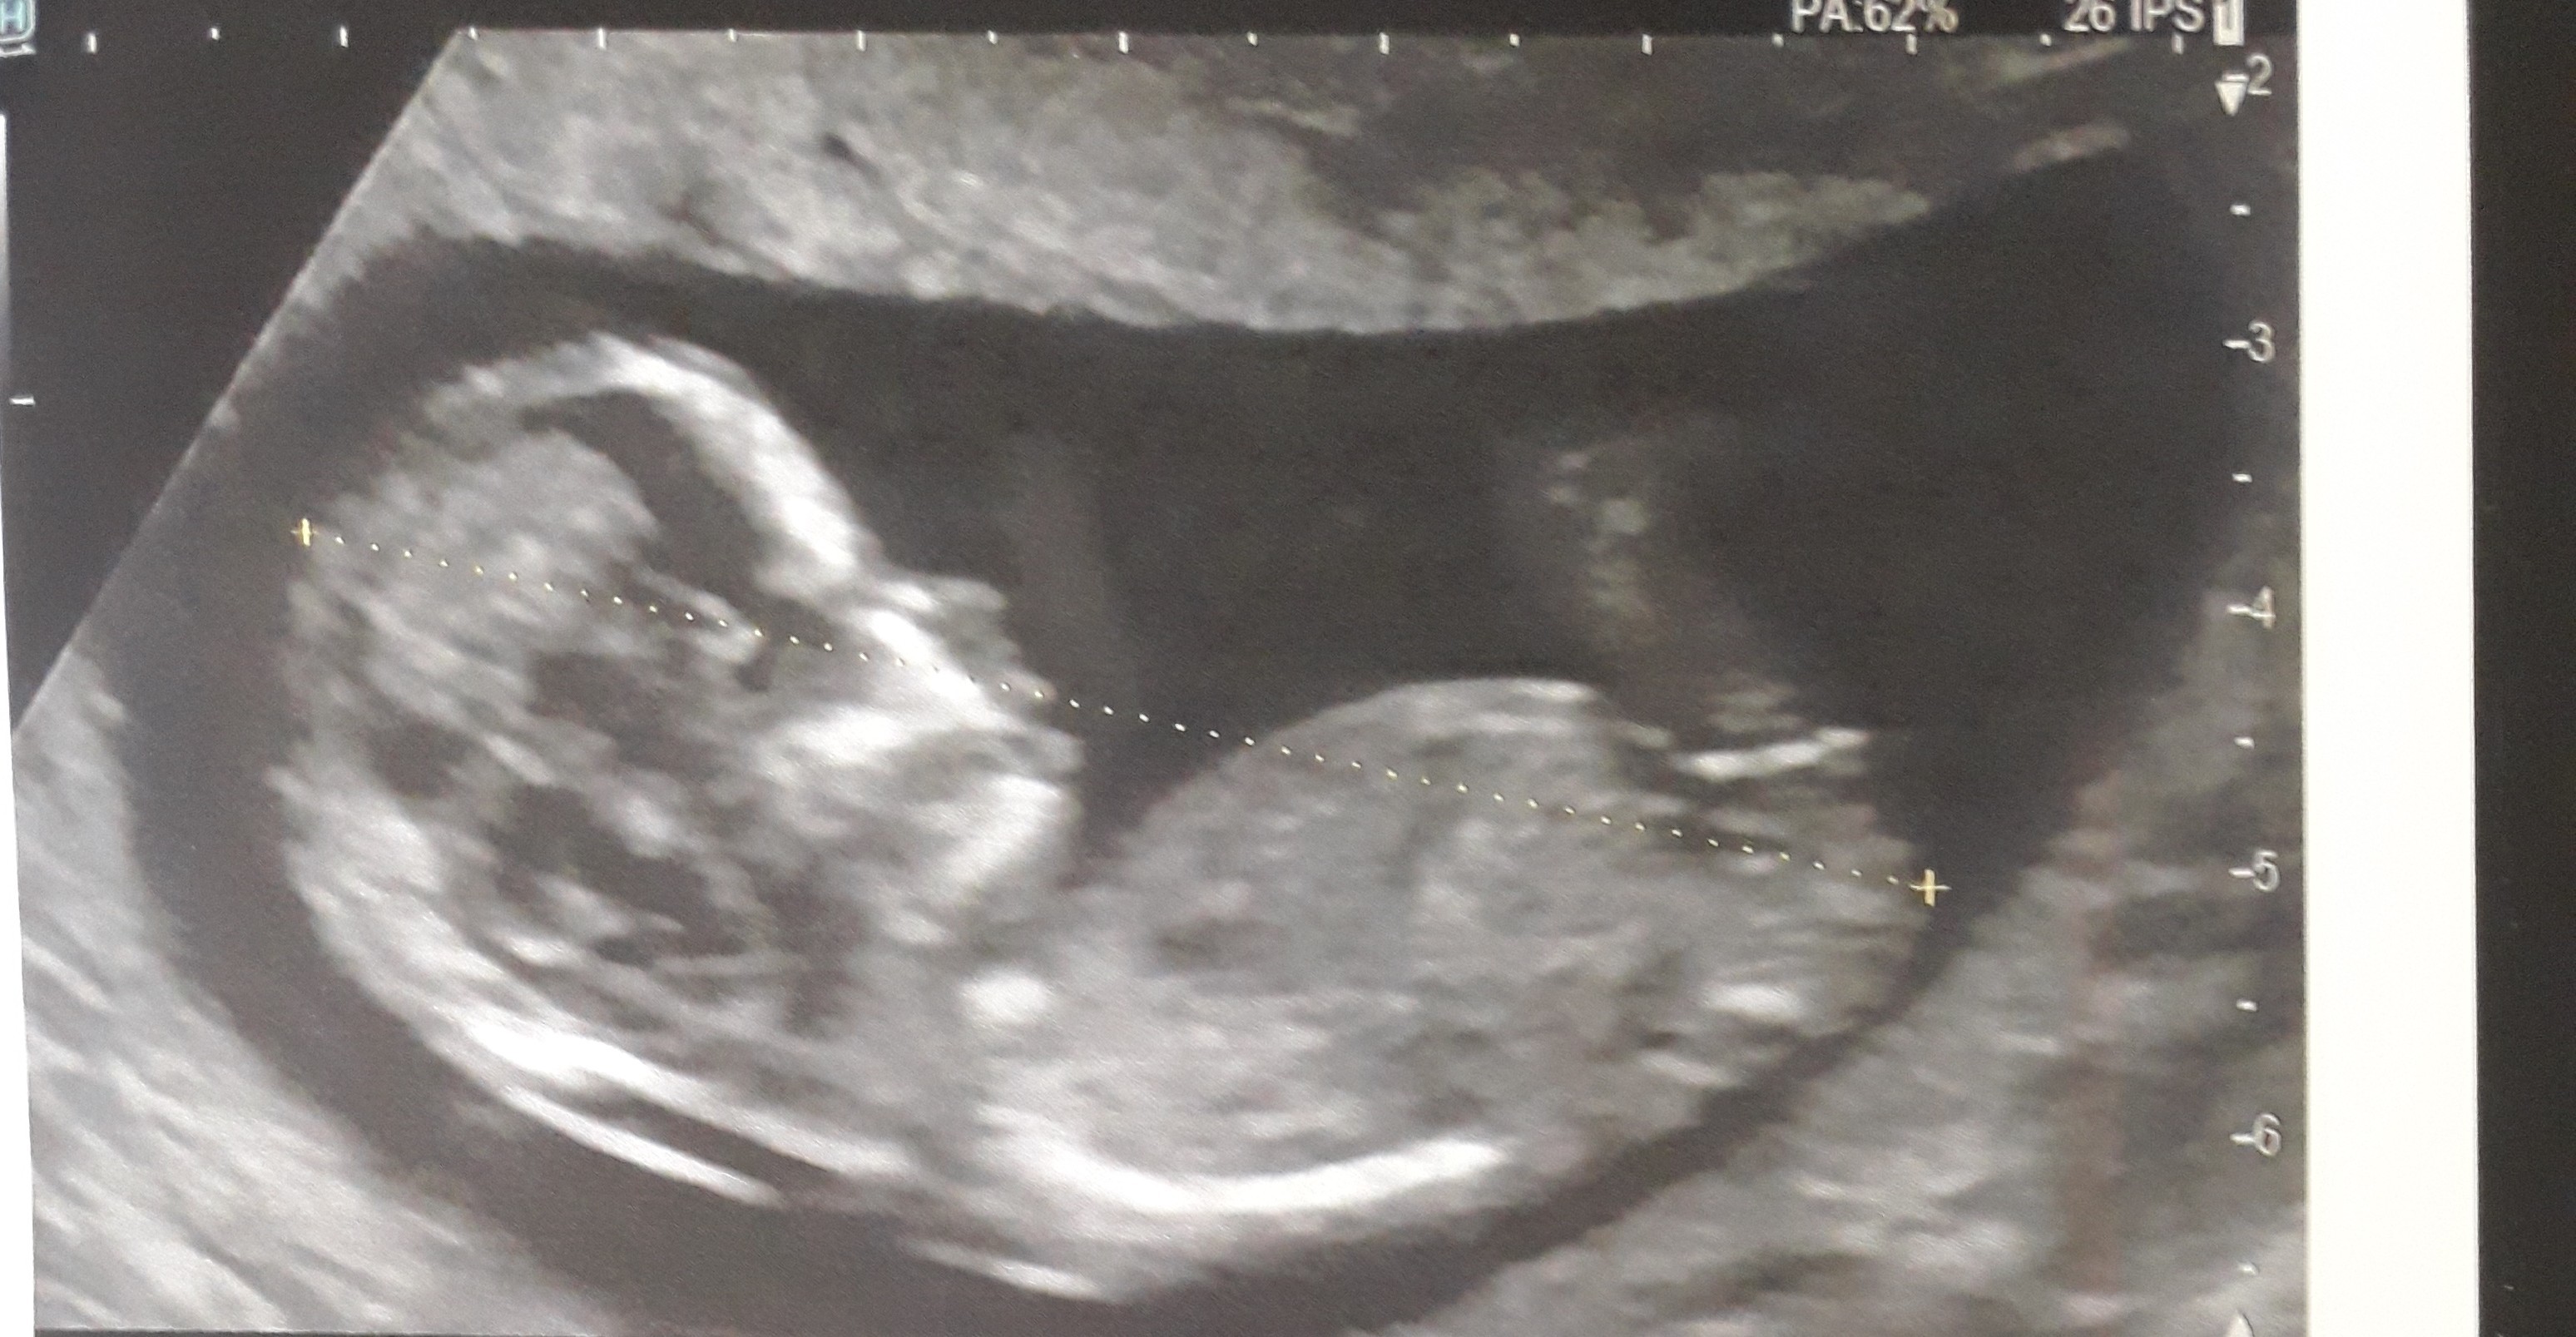

A 14 SA (semaines d'aménorrhée), soit 12 semaines de grossesse effective, c'est bientôt la fin de votre troisième mois de grossesse Votre corps continue de changer, notamment la poitrine et surtout le ventre qui s'arrondit Bébé poursuit quant à lui sa croissance, ses organes sont désormais opérationnels C'est aussi le moment d'envoyer votre déclaration de grossesse Tableau de biométrie foetale DISTANCE CRANIO CAUDALE (TETE FESSES ) EN MILLIMETRES à 5 semaines d'aménorrhée 1 à 2 mm à 7 semaines d'aménorrhée 8 mm à 9 semaines d'aménorrhée 25 mm à 10 semaines d'aménorrhée 33 mm à 11 semaines d'aménorrhée 43 mm à 12 semaines d'aménorrhée 55 mm à 13 semaines d'aménorrhée 68 mm à 14 Votre commentaire date un peu mais je suis dans la même situation que vous a l inverse j ai 3 garcons et 1 fille et je suis enceinte de mon 5ème bébédepuis lapremiere écho la gynéco m a dit que c était encore un garconje suis à 22 sa je vais avoirmon écho morpho la semaine prochaine mais depuis 12 sa je suis déçue de savoir

La première différence qui va commencer à apparaître sur une écho concerne l'inclinaison du bourgeon Chez les garçons, il aura tendance à remonter alors que chez les filles, il restera plus à plat C'est pour cette raison que la méthode du bourgeon génital détermine l'angle formé par le tubercule génital (lignes du bas dans les Tout avait pourtant bien commencé J'aurai du me méfier ! mon bébé a été diagnostiqué avec les intestins hyperéchogènes à mon écho de 19 semaines et puis après une écho plus poussée à 21 semaines, ils nous ont expliqué que tout était beau et que plusieurs choses pouvait expliquer que les intestins apparaissait blancs à l'écho, que ce n'était pas nécéssairement un marqueur de maladie ou autre

Une tête, un corps, des membres il n'est plus le petit point sur le côté de l''uterus que j'avais vu début septembre Bébé 2 va très bien Il pousse normalement Bébé 2 est paisible Il est tranquillou avec ses deux petites mains près de sa bouche et ses 2 jambes repliées 2) Déterminer le sexe du bébé Alors, je préfère prévenir deux fois qu'une, ce n'est pas une science, je ne suis pas médecin, et c'est juste une petite astuce qui est quand même beaucoup plus éfficace que le pendule Je peux très bien me tromper, mais en général c'est fiable à au moins 70% si l'échographie est lisible Si c'est une filleOn dit de moi que j'ai une sacrée répartie mais quand on est maman, on a plutôt intérêt à ne pas se laisser marcher sur les pieds